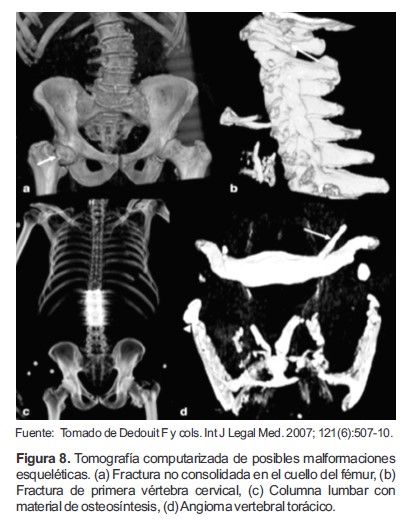

G. Identificación de cadáveres NN (No Name)

La TC también ha sido usada para la identificación de sujetos, ya que esta puede detectar características propias de los cuerpos, tales como son implantes, cirugías o fracturas antiguas (59). Puede verse, por ejemplo, para los estudios realizados por Dedouit y colaboradores, a 35 cuerpos; de las 35 exploraciones, diez revelaron malformaciones esqueléticas, fracturas antiguas, o fracturas no consolidada en el cuello de fémur derecho (Figura 8a); una fractura de la primera vértebra cervical a nivel pedicular izquierdo (Figura 8b); una columna lumbar con material de osteosíntesis (Figura 8c); una calcificación en el ligamento tirohioideo izquierdo (Figura 8d), espondilolistesis bilateral ístmica de la quinta vértebra lumbar, y un angioma vertebral torácico (60, 61).

Algunas anomalías esqueléticas fueron confirmadas por las investigaciones de la policía: El fallecido quien tuvo el material de osteosíntesis tenía una historia pasada de la fractura de la columna y la cirugía, el sujeto que presento fractura de vértebra cervical pedicular izquierda tenía un historial reciente de fractura cervical. A excepción de la prueba del material de osteosíntesis, ninguno de los hallazgos mencionados se ve durante la autopsia convencional (60).

Figura 8. Tomografía computarizada de posibles malformaciones esqueléticas. (a) Fractura no consolidada en el cuello del fémur, (b) Fractura de primera vértebra cervical, (c) Columna lumbar con material de osteosíntesis, (d) Angioma vertebral torácico.